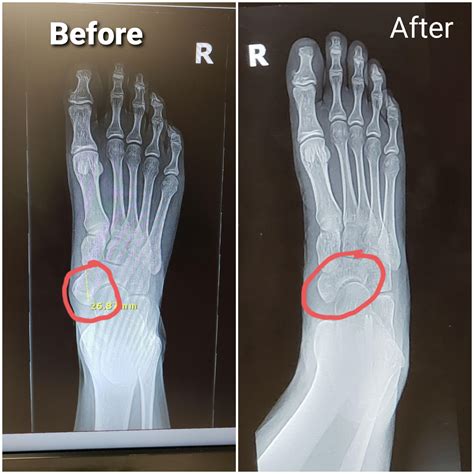

When Surgery is Necessary

Surgery is typically considered a last resort. It may be required if conservative treatments fail to provide relief, or if there is a non-union fracture (a fracture that refuses to heal on its own). For accessory navicular syndrome, surgical removal of the accessory bone may be necessary if conservative care does not reduce chronic pain.